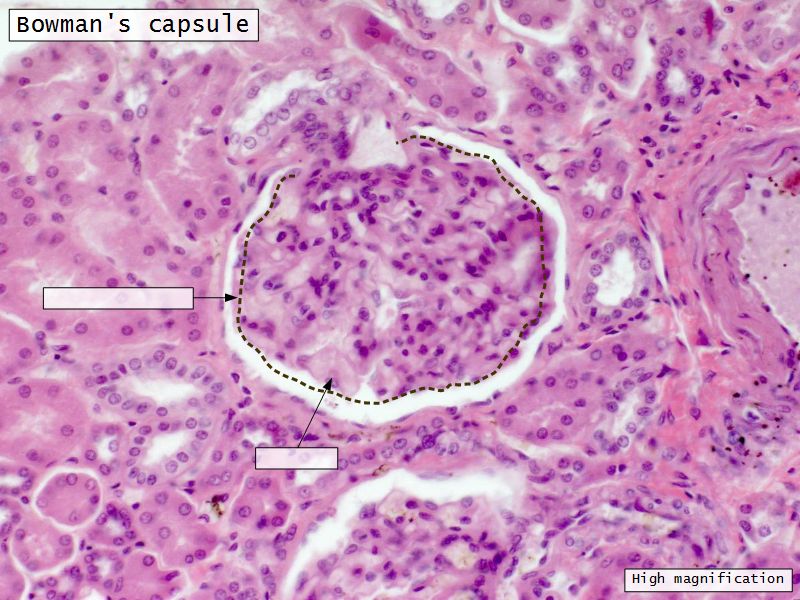

Renal corpuscle

- Tuft of capillaries

- grow into

- Blind end of nephron

- Several layers of epithelium

- Two sides

- Vascular pole

- Tubular pole

Epithelium layers

- Capillary endothelium

- Visceral layer of epithelium

- Podocytes

- Resting on glomerular basement membrane

- Capsular space

- Parietal layer of epithelium

- Simple squamous epithelium